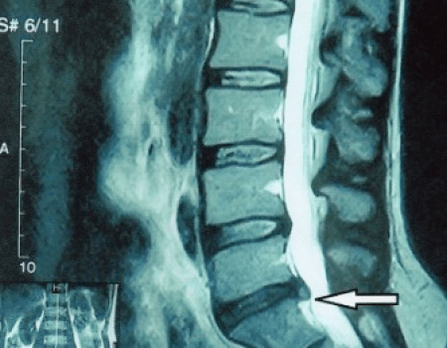

gerinclemez kiemelkedése MRI-vizsgálaton

Miért történt ez? Idővel a rostos gyűrű fokozatosan elhasználódik. Már nem tud nyúlni, csak kifelé, a korongon túlnyúlik, vagy eltörik. A mag nem továbbítja és átalakítja a függőleges terhelést radiális terheléssé. Az életkor előrehaladtával a stressz fokozatosan felhalmozódik a porckorongok belsejében, és szerkezetük megváltozik. Ha mindezen folyamatok egy külön lemezen átkerülnek a teljes gerincoszlopra, akkor a klinikán egy osteochondrosis nevű állapotot kapunk. Most elkezdhetjük meghatározni.

Mivel maguk a porckorongok csak CT vagy MRI segítségével láthatók, mágneses rezonancia és röntgen komputertomográfia javasolt a porcok belső szerkezetének és a képződmények, például a kiemelkedések és a sérvek tisztázására. Így ezen módszerek segítségével pontosan felállítják a diagnózist, és a tomográfia eredménye jelzés, sőt aktuális iránymutató az idegsebészeti osztályon fellépő sérv műtéti kezelésére.